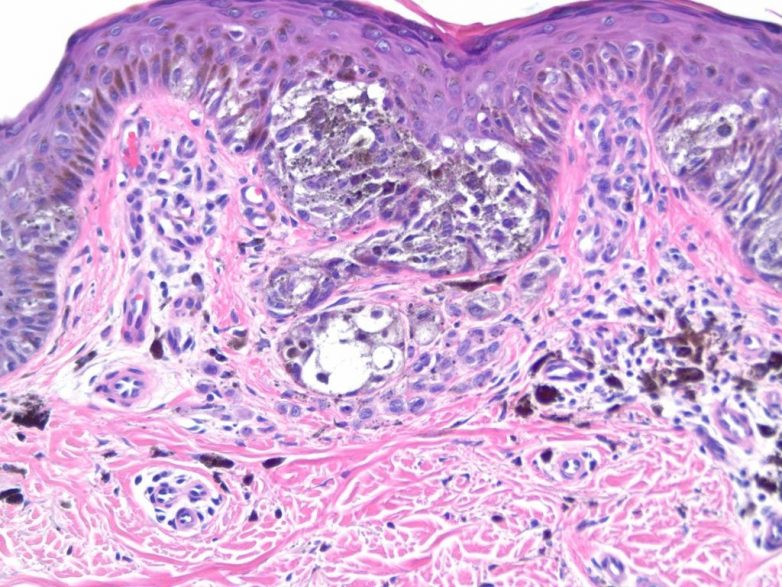

Онкологи разгадали почти вековую загадку метаболизма раковых клеток и нашли перспективные мишени для будущих лекарств от меланомы.

Ученые из Медицинского исследовательского института Стэнфорд-Бернхам (США) выяснили, что даже если лактатдегидрогеназа А исключена из метаболизма клетки опухоли кожи (меланомы), через некоторое время гликолиз возобновляется — и раковая клетка снова получает энергию, растет и делится. Медики также установили, что на замену LDHA приходит другое вещество — фактор транскрипции ATF4: мутантная клетка вскоре переключается на сигнальный путь с участием этого вещества и возобновляет жизнедеятельность.

После того как ученые блокировали LDHA в клетках меланомы, последние перестали использовать АТФ в качестве источника энергии: вместо этого они начали «поедать» аминокислоту глутамин. При этом в клетках заметно увеличилось производство ATF4, благодаря которому возрастало поступление глутамина в клетку извне. Приток аминокислот, в свою очередь, активировал выработку фермента mTOR — регулятора клеточного роста и выживания, благодаря чему клетки продолжали расти.

Руководитель исследования Гаурав Патрия (Gaurav Patria) и его коллеги полагают, что одновременное воздействие на LDGA и mTOR может остановить анаэробный гликолиз в клетках меланомы, их рост и деление и даже спровоцировать гибель раковых клеток. Есть смысл также попробовать блокировать другие ферменты, участвующие в метаболизме глутамина и сигнального пути ERK, для которых существуют эффективные ингибиторы.

Данные, полученные Патрией и его коллегами, не только предполагают новую мишень для будущих лекарств от меланомы, но и помогают разобраться в причинах существования эффекта Варбурга. «Возможно, дело в том, что для раковых клеток проще не получать АТФ, а использовать для роста аминокислоты, и отказ от аэробного гликолиза обусловлен этим», — объясняет Патрия.